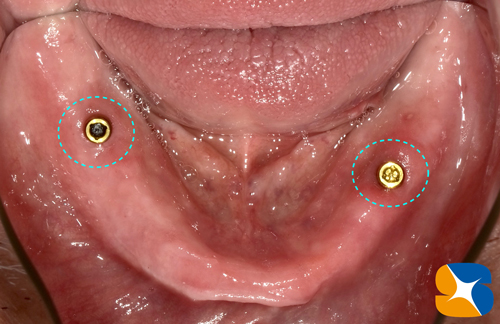

昨年の暮れにインプラントを移植された方の初めての定期検診。

72歳の男性。永年、上も下も全部入れ歯を使っておられました。上の全部入れ歯は、ポリグリップで外れないようにがっちりキープ出来ています。しかし、下の全部入れ歯は、大きな口を開けると動いて外れそうになるので何か良いものはないかな?がこの治療の始まりでした。

下のアゴに2本の(ロケーター)インプラントを移植しました。

左利きの患者様が、全部入れ歯を取り外ししやすいように設計しています。

たった2本のインプラントですが、全部入れ歯は全く動きません。

全部入れ歯を外してみたところ。

全部入れ歯の裏側はこのようになっています。お口の中には凸部が入り、全部入れ歯の内側には凹部が組み込まれ、両者はパチッと合体します。